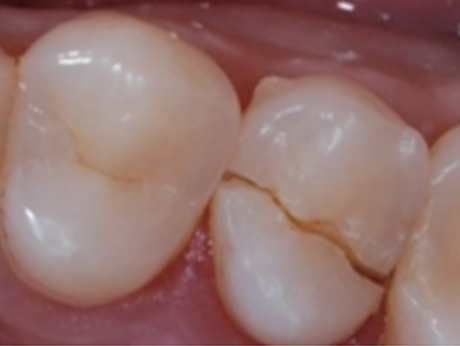

신경제거 후 신경으로부터 받던 영양분을 공급받지 못해 약해진 치아는 작은 충격에도 금이 가거나, 부러지거나, 깨져버리기 때문에 단단한 크라운을 씌워 치아를 보호해야 합니다.